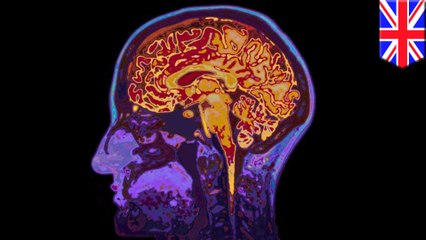

World Alzheimer's Day: Spanish scientists trial vaccine

On September the 21 World Alzheimer's day aims to raise awareness about the most common form of dementia.br br Around 36 million people are affected by the disease worldwide, a number which is expected to rise to more than 115 million by 2050.br br For now there is no cure but Spanish scientists, who have been working on vaccine, say they could soon start clinical trials on humans.br br ...